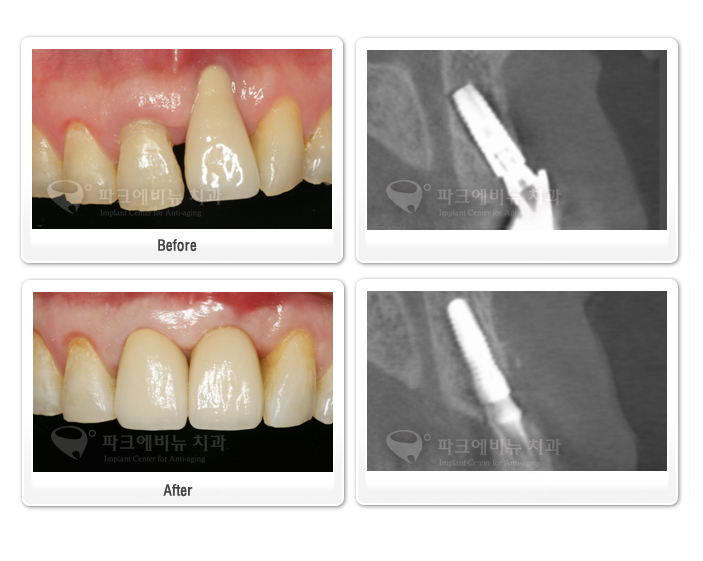

부산에서 오신 사진의 환자분은 몇 년 전에

앞니 임플란트 수술을 받으셨다고 합니다.

그때 임플란트의 식립 위치, 각도 등의 문제로

앞니 보철물의 모양이 정상 치아에 비하여

상당히 길쭉한 모양으로 만들어져 있었습니다.

그래서 엑스레이 촬영과 구내 사진촬영,

얼굴 사진 촬영 등의

환자 정보 분석을 통한 계획 하에 임플란트

재 수술에 들어가게 되었습니다.

먼저 잘못 식립되어있던 임플란트를 제거하였습니다.

임플란트가 제거된 자리는 비어있기 때문에

뼈의 치유를 촉진시키기 위해 뼈를 이식하였습니다.

또한 임플란트의 잘못된 위치 때문에 내려가 있던

잇몸의 레벨을 정상 범주로 되돌리기 위해서

입천장에서 떼어낸 조직을 앞니 잇몸 부위에 이식했습니다.

신경 치료가 되어있던 옆 대문이의 크라운을 벗겨내고

브릿지 형태로 임시치아를 만들어 보철물이 완성되기 전까지 사용했습니다.

3개월의 치유 기간을 거친 뒤,

잇몸은 거의 정상 레벨로 회복되었고

잇몸 뼈 또한 임플란트 수술을 시행할 수 있을 정도로

경화되었다고 판단해 임플란트 재 식립 수술을 시행했습니다.

그리고 4개월 뒤, 임플란트와 뼈가 단단히 결합하여

보철물을 만들기 위한 본을 떠서 일주일 뒤,

도자기로 된 보철물을 끼워드렸습니다.